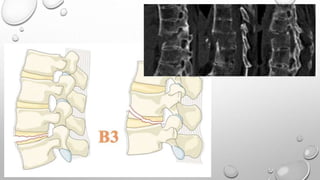

Tipo B

Describe falla del complejo ligamentario posterior

o el ligamento longitudinal anterior.

B1: Disrupción de la banda de tensión trans-osea

/ Fractura oportunista

B2: Disrupción de la banda de tensión posterior

B3: Hiperextensión